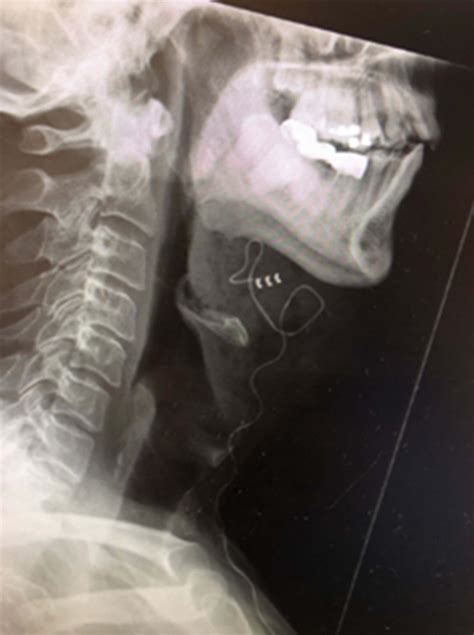

- A pulse generator, similar to a pacemaker, which is implanted in the chest.

- A sensing lead, placed between the ribs to monitor breathing patterns.

- A stimulation lead, attached to the hypoglossal nerve in the neck.

The pulse generator detects breathing patterns through the sensing lead. When it detects an apneic event, it sends electrical impulses to the stimulation lead, which in turn stimulates the hypoglossal nerve. This stimulation causes the tongue to move forward, opening the airway and allowing for uninterrupted breathing.